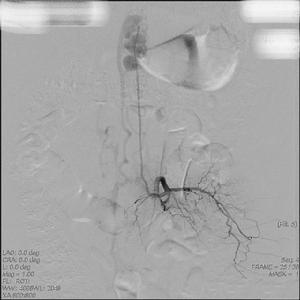

當在強化CT或MRI上提示此診斷時,選擇性脊髓動脈造影是確定診斷的方法。在血管造影的過程中,脊髓前動脈是可以辨認的,與硬膜動靜脈畸形相關的血供也可確定。病變的所有滋養動脈都應該確定清楚,以防止術後動靜脈瘺交通支復發,有時靠近頭顱的硬膜動靜脈瘺可能有脊髓靜脈交通,並且可以引起脊髓靜脈高壓和脊髓病。在這些病人中,為確診這類不常見的疾病有必要進行選擇性的頸外動脈和頸內動脈注射造影劑作頸動脈造影。

2、ⅡⅢ型診斷髓內動靜脈畸形病灶可通過T1加權像上的流空徵象加以識別。在T2加權像上常並有脊髓內出現異常信號,脊髓周圍的流空徵象提示脊髓病變周圍的部分。脊髓動脈造影在確定髓內病變上是必要的,但在區分Ⅱ型和Ⅲ型病變上並不總是有幫助。選擇性主動脈插管以及椎動脈、頸動脈和髂腰血管的插管造影在確定髓內病變供應的滋養動脈上是有必要的。背側和腹側的根血管經脊髓前動脈和脊髓後動脈分支供應動靜脈畸形。脊髓前動脈可能終止於髓內動靜脈畸形,或仍可能作為一段血管,可以確定脊髓動脈瘤和靜脈曲張。

3、Ⅳ型診斷磁共振成像有時顯示大的脊髓周圍的流空徵象主要表現為擴張明顯的硬膜內靜脈回流,這些畸形常常出現在胸腰連線處圓錐附近和馬尾近端。選擇性血管造影可顯示脊髓前動脈到動靜脈瘺的分布和回流靜脈。